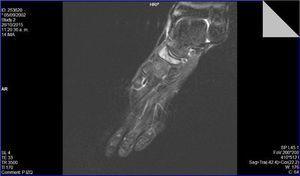

Se realizaron radiografías en proyecciones anteroposterior y oblicua, que mostraron un primer radio corto y esclerosis del escafoides tarsiano con aplanamiento anteroposterior, y un acuñamiento del aspecto lateral dando una morfología en forma de «coma» (Figura 1). En la proyección lateral se observó un trazo de fractura de 45° de inclinación. Con estos hallazgos se suspendió la actividad deportiva y se mantuvo en descarga durante 4 semanas. Se realizaron una resonancia magnética y una tomografía computarizada. La tomografía mostró un trazo de fractura en el escafoides izquierdo y signos de lesión osteocondral (Figura 2). La resonancia mostró un extenso edema intraóseo del escafoides tarsiano, aplanamiento del aspecto lateral, un área con marcada alteración de señal sugestivo de osteonecrosis y una imagen lineal de morfología cóncava que afectaba el aspecto dorsal y lateral del escafoides (Figura 3).

Figura 3. Resonancia magnética: secuencia potenciada en T2 con saturación grasa. Alteración en la morfología del escafoides tarsiano, con edema medular en el escafoides.